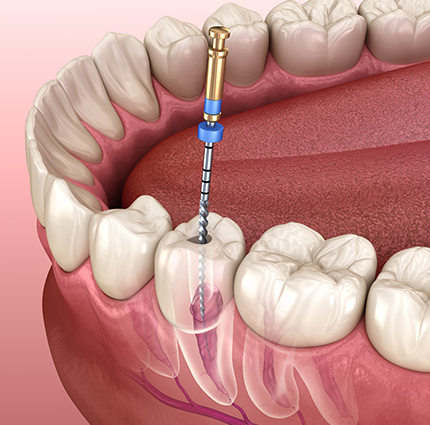

- 작은 보철 하나에도

세심한 차이를 담아내기 위해 정성을 다하겠습니다. - 치과보철과 전문의

- 황 혜 경 원장 /라미네이트, 틀니, 심미보철

- Implant- assited removal partial(IARPD) rehabilitation in a patient exhibiting mandibular prognathism due to decreased vertical dimension : a case report, The Journal of Korean Academy of Prosthodontics 63.1